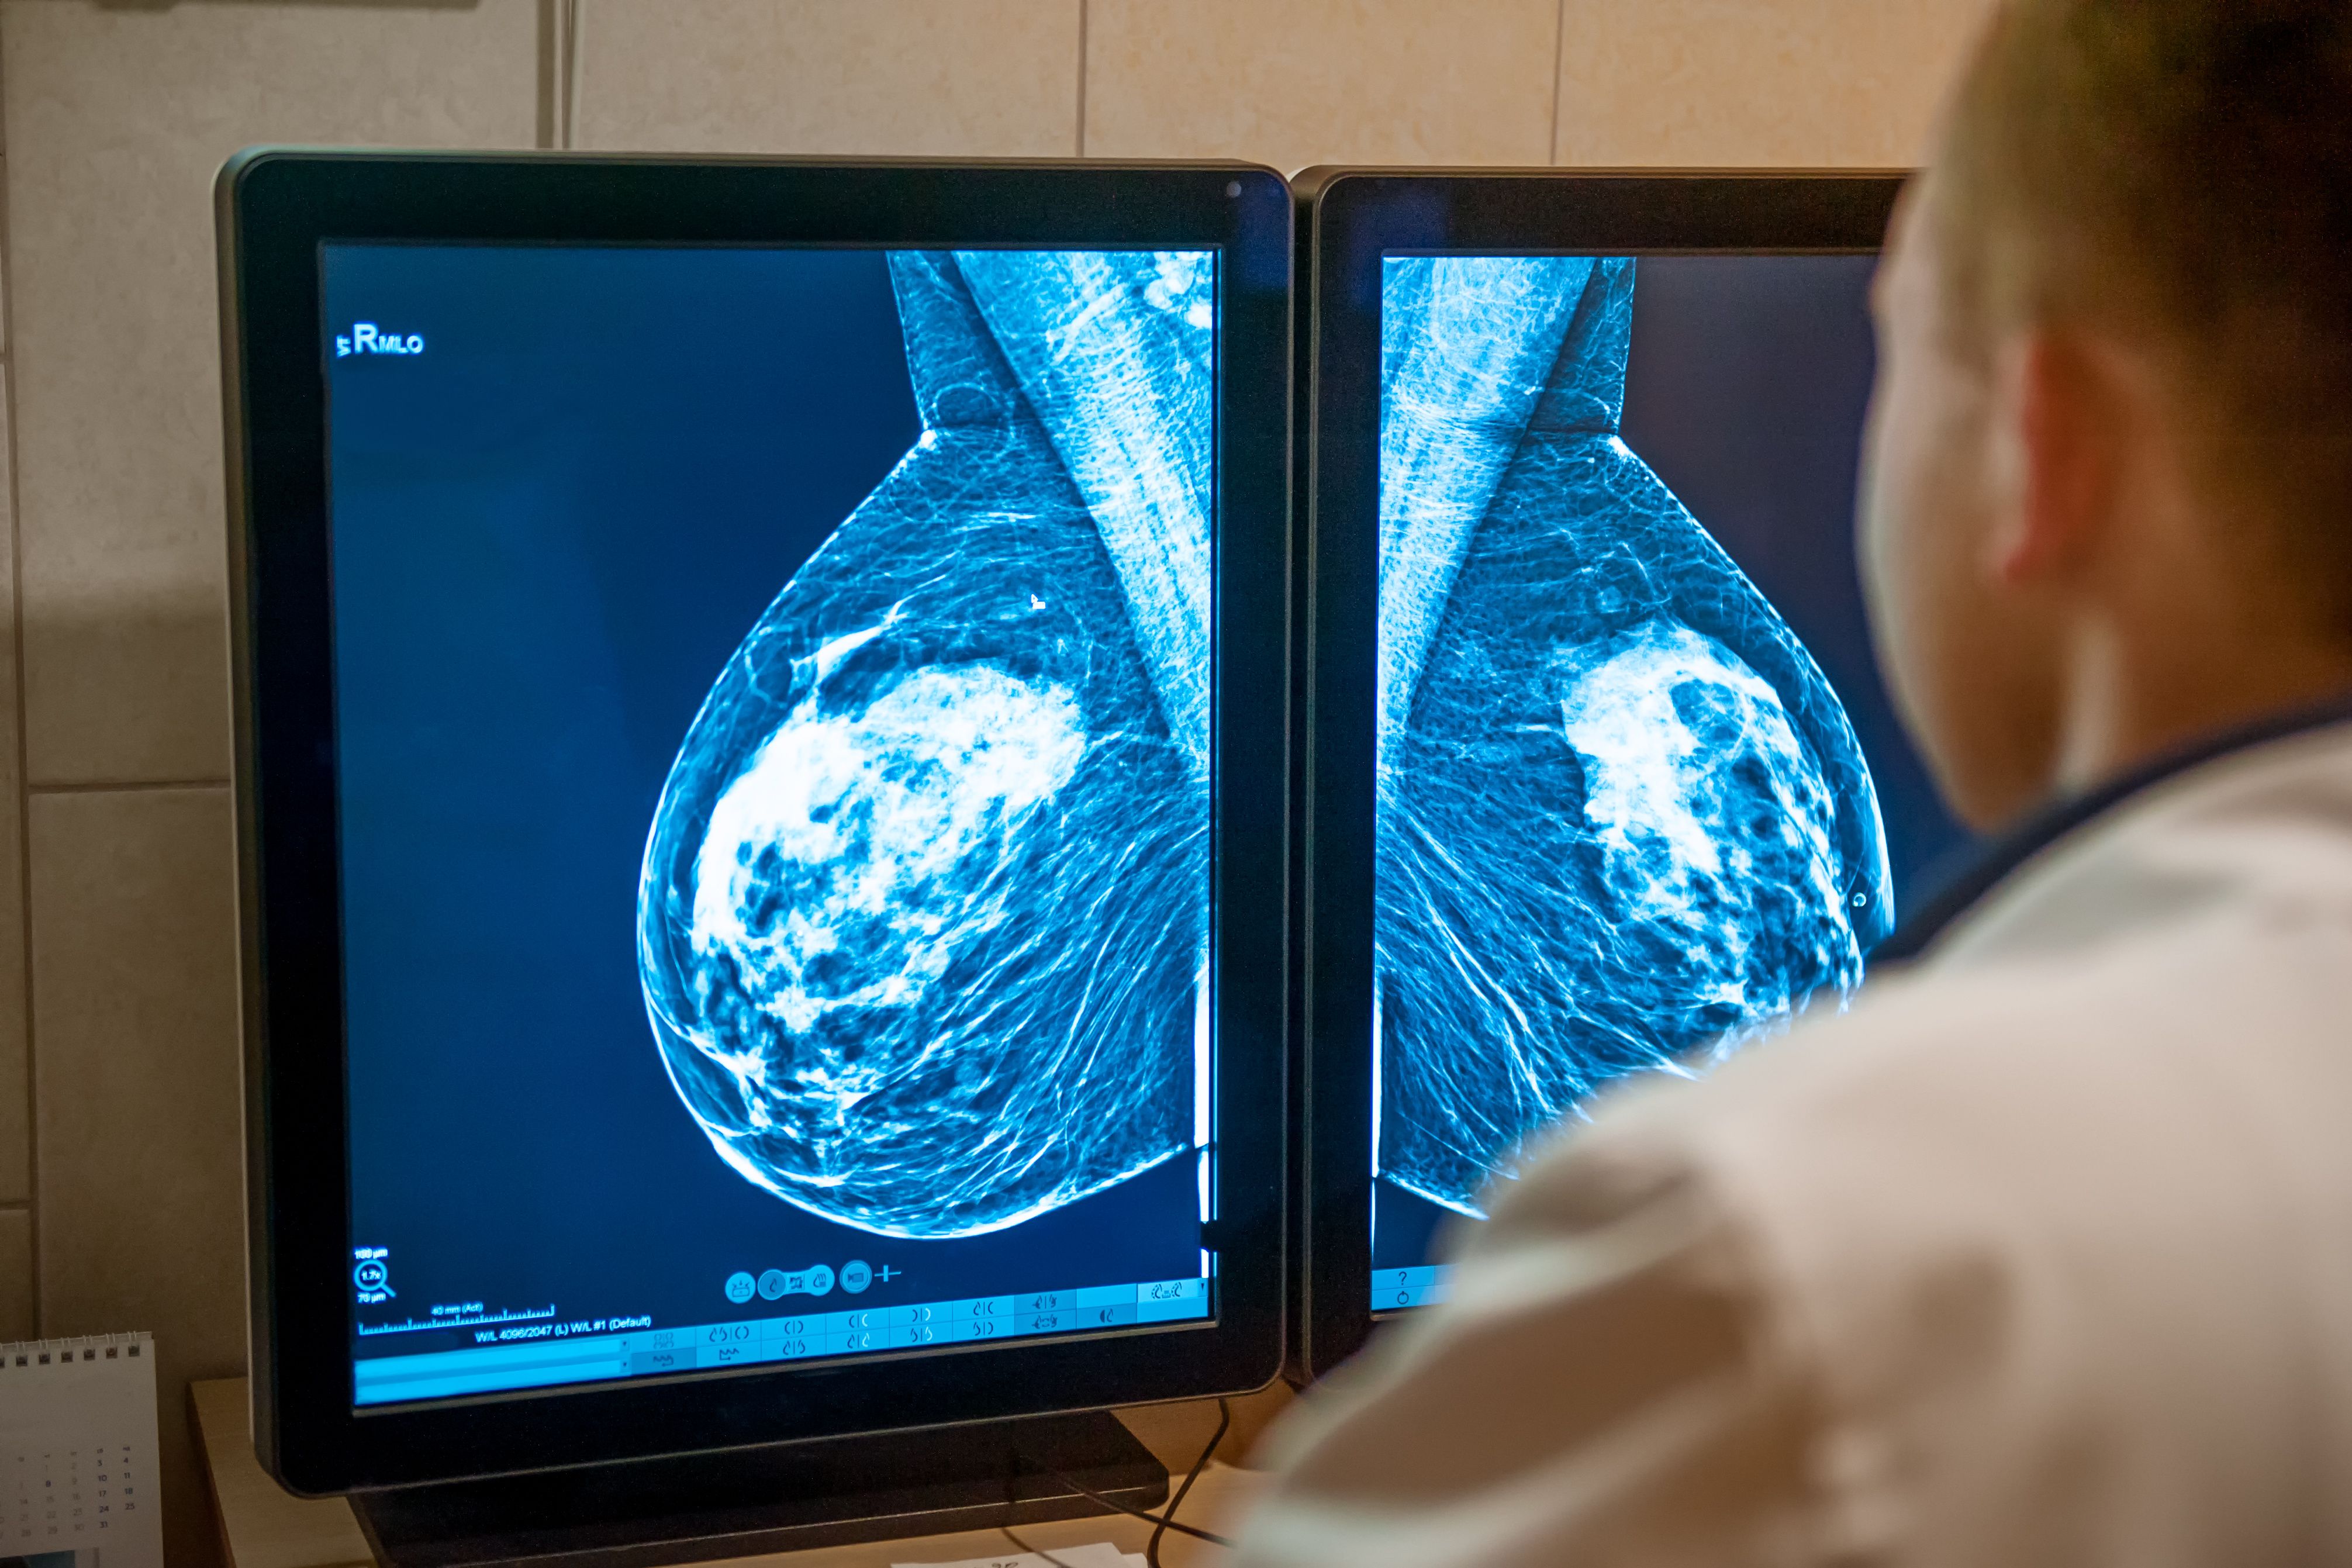

AI-assisted breast cancer screenings aid in reducing radiologists' workload when certain of its analysis. | Image Credit: okrasiuk - stock.adobe.com

The study introduced an AI model to mammogram screenings that outputs the probability of malignancy (POM) and a measure of its uncertainty. Researchers proposed a hybrid reading approach where recall decisions for additional screenings made by the model were only assessed for a double reading by a radiologist if the predictions were deemed confident by the model itself.